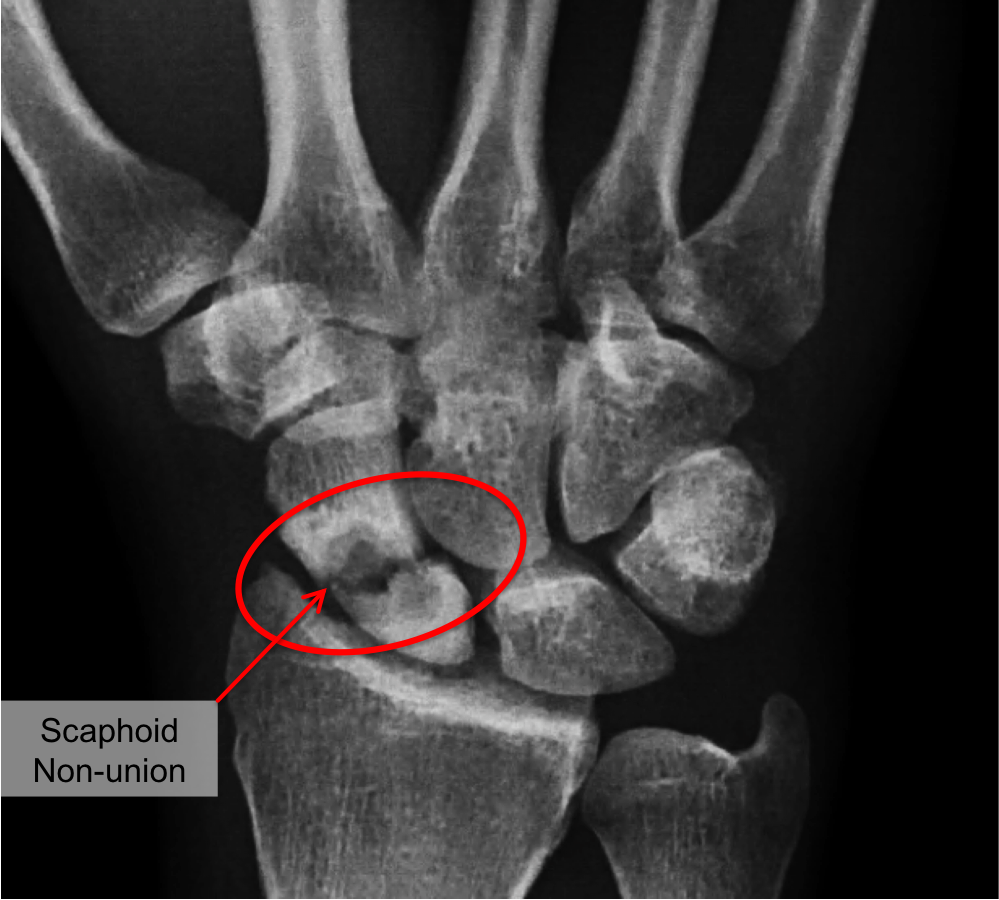

불유합(Nonunion)FDA(The U.S. Food and Drug Administration) 에서는 손상 후 최소 9개월이 경과한 상태에서 3개월 동안 골유합 진행 모습이 보이지 않을때 로 정의하고 있습니다. 예외적으로 장골에서는 최소한 6개월 경과 후 의심할 수 있으며, 혈류가 좋은 고관절 골절의 경우 3개월만으로도 진단이 가능합니다. 불유합은 위치나, 감염의 유무, 병인 등으로 나뉠 수 있는데 위치는 골단, 골간단, 골간 으로 나뉠 수 있습니다. 병인으로는 비후성 불유합(혈류는 적절하여 가골이 적절하게 생기나 stability 부족), 빈영양 불유합(적절한 혈류 + 가골 형성 거의 안됨), 위축성 불유합(혈류가 부적절) 등으로 나뉠 수 있습니다.